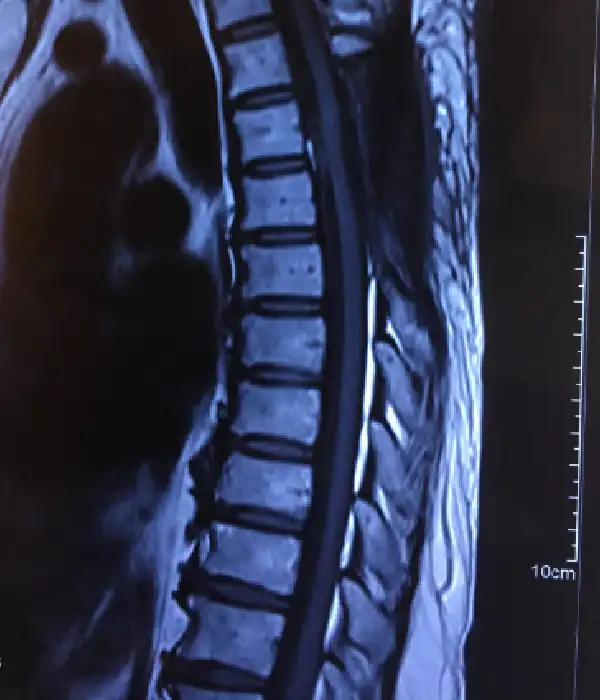

Degenerative Thoracolumbar Spine Disorders

Degenerative thoracolumbar disorders are becoming increasingly prevalent as patients have longer, healthier, and more active lives. While much of the treatment is nonsurgical, there are certain conditions that require surgery. Some degenerative diseases can be easily treated with small, minimally invasive procedures, but others require large, reconstructive operations. The spine surgeons at Kauvery Advanced Spine Centre have considerable experience treating the entire spectrum of degenerative disorders, as well as in-depth knowledge of the success rates of each procedure. Mini open and minimally invasive transthoracic disc surgery is performed here.

- Disc herniations

- Disc Stenosis

Lumbar disc prolapse

Lumbar stenosis